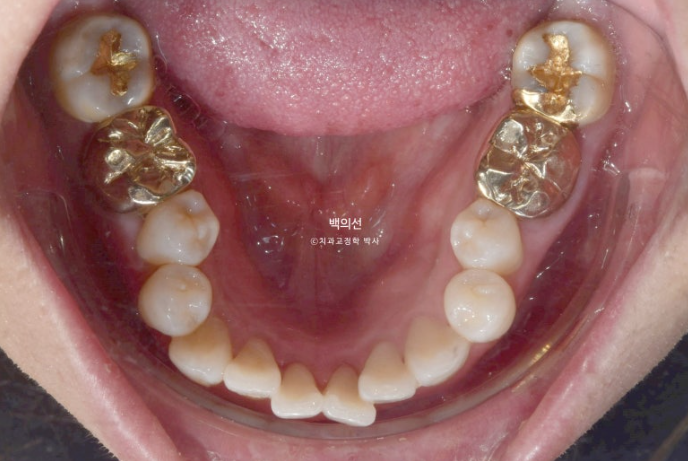

그런데 파란 화살표 부분에 큰어금니가 하나 없습니다.

오래 전 큰어금니가 빠진 부분을 브릿지로 치료해 놓은 상태입니다.

치료의 편의성을 위해서는 작은어금니 4개 발치가 필요하나 브릿지 자체가 오래되기도 해서 파란 화살표쪽 분악은 추가적인 소구치 발치 없이 브릿지를 잘라내어 큰어금니 빈공간에 이용하기로 합니다.

그러면 작은어금니 발치갯수를 4개에서 3개로 줄일 수 뿐더라 오래전 큰어금니 빠진 자리를 임플란트 없이 교정으로 메꿀 수 있는 장점이 큽니다.

브릿지를 잘라낸 모습입니다.

클리피씨 치료를 선택하셨고 치료에 들어갔습니다.